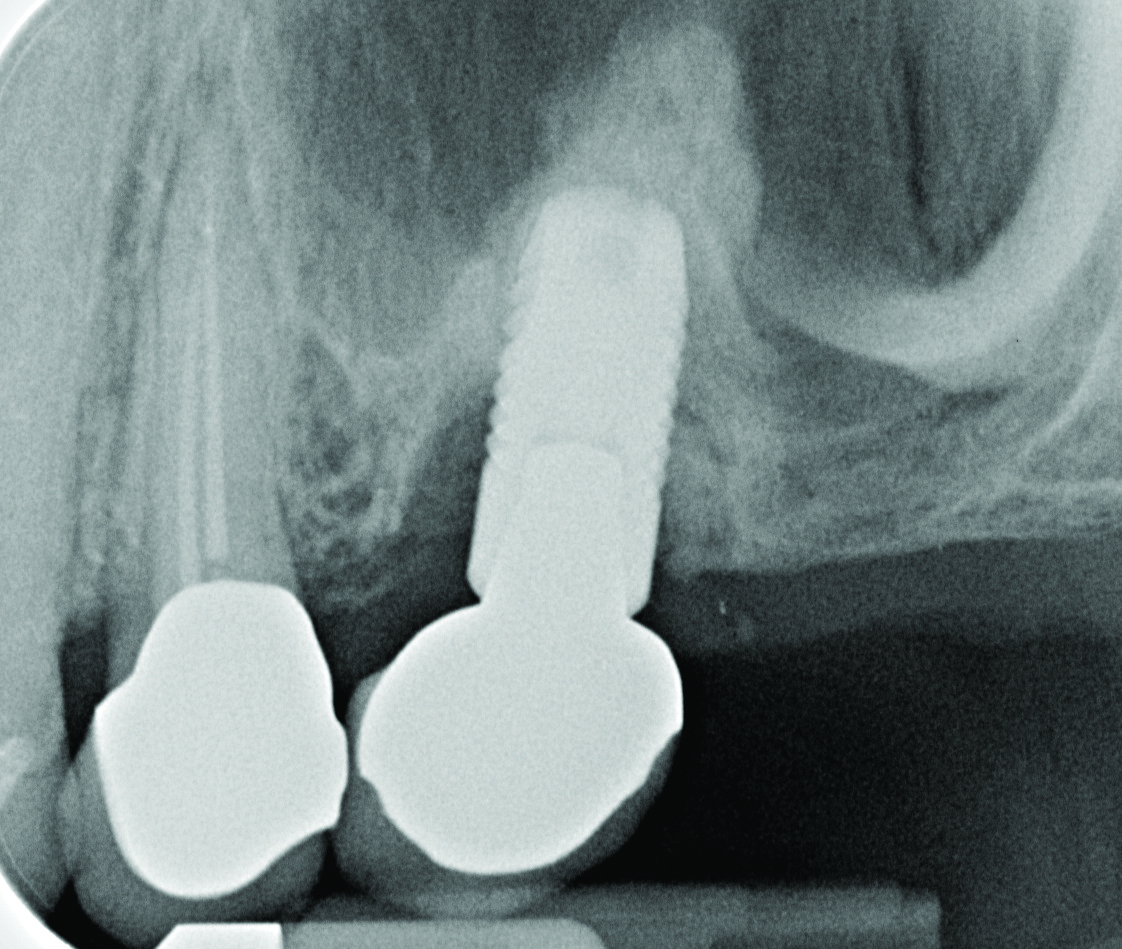

Radiograph of this same area. Note that there is no indication of bone loss and a long abutment collar. Hence, the diagnosis of peri-implant mucositis is given.

Figure 2

Radiograph of the area suggests moderate to advanced bone loss at the mesial aspect making the diagnosis peri-implantitis.

Figure 4